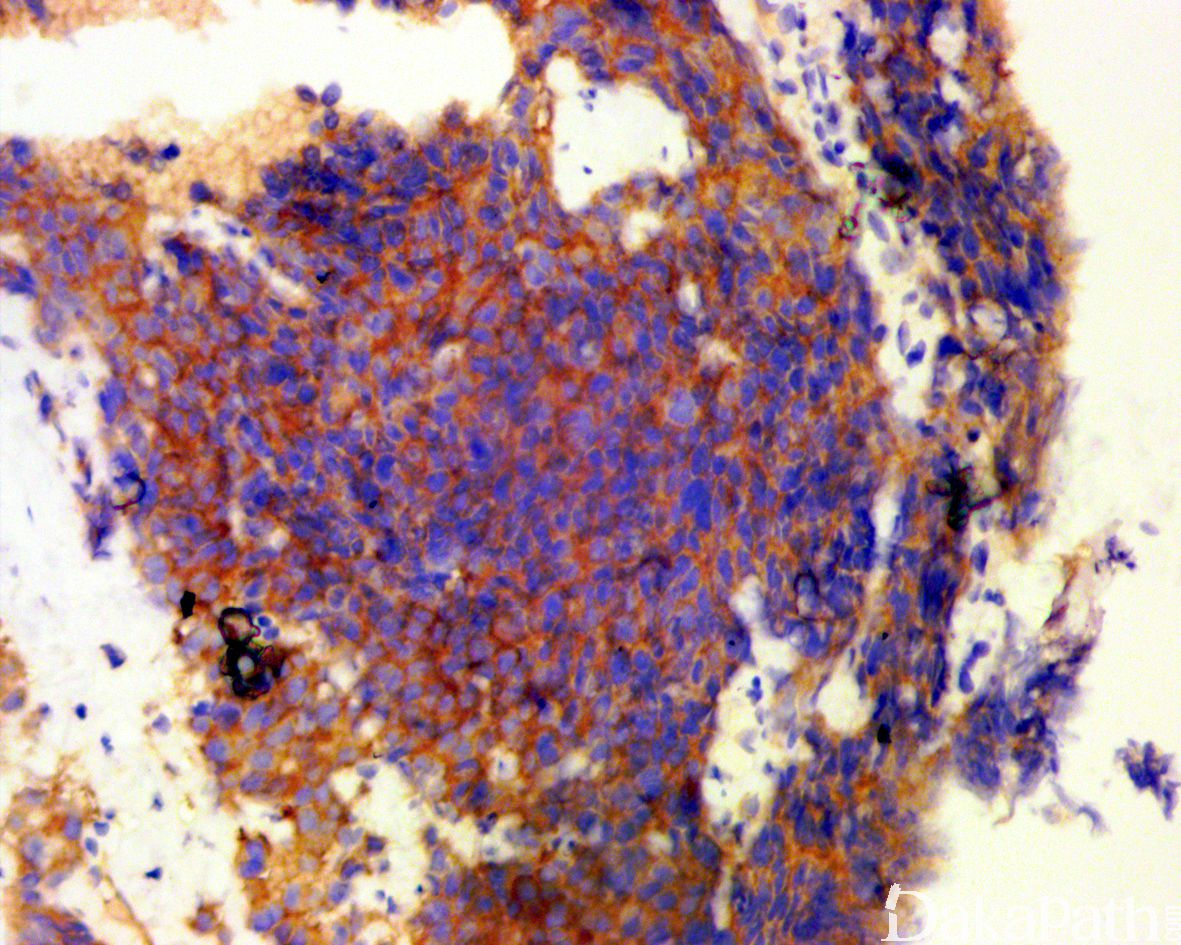

免疫组织化学染色:

免疫组化对于前列腺小细胞癌的诊断并非必须,但通常用于对形态学印象的证实。瘤细胞通常 CAM5.2(核旁逗点状)、CgA、Syn、CD56. NSE、TTF-1(> 50%的病例阳性)、P53 等常阳性,AR,NKX3.1,PSA 及 PAP 通常阴性或仅为局灶阳性,约 1/3 可表达 P63 和高分子质量角蛋白(通常为局灶),Ki67 > 50%